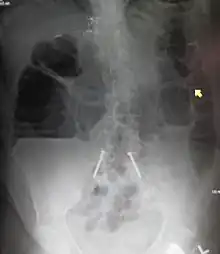

A small bowel obstruction as seen on CT

Small bowel dilation on CT scan in adults[11]

<2.5 cmNon-dilated

2.5-2.9 cmMildly dilated

3-4 cmModerately dilated

>4 cmSeverely dilated